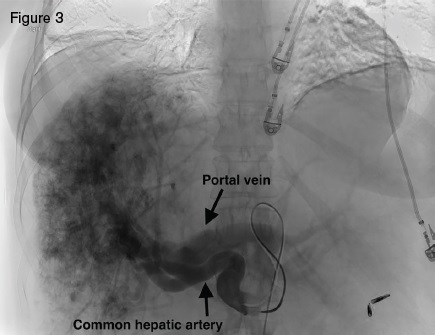

Angiogram displaying large hepatic arteries with shunting primarily from hepatic artery to portal vein.

A 51-year-old woman with HHT was referred for management of recurrent epistaxis, GI bleeding, iron deficiency anemia, large bilobar hepatic AVMs, and worsening ascites. Gastric AVMs were previously managed with endoscopic argon plasma coagulation. She required regular intravenous iron and occasional blood transfusions to maintain a hemoglobin of seven to 10 g/dL. Elevated liver enzymes two years earlier prompted an ultrasound that demonstrated hepatic AVMs. Magnetic resonance imaging (Figure 2) demonstrated a macronodular liver with diffuse AVMs involving both hepatic lobes, ascites, and splenomegaly. Angiogram demonstrated large hepatic arteries with shunting primarily from hepatic artery to portal vein (Figure 3). She primarily reported weakness, dyspnea on exertion, and worsening ascites requiring weekly six- to seven-L paracentesis.

Hepatic AVMs occur in as many as 74 percent of HHT patients.1 The majority of HHT hepatic AVMs, however, are asymptomatic, making routine screening inadvisable.2 Large hepatic AVMs with extensive arterio-hepatic venous shunting can lead to high-output cardiac failure. When shunting is predominantly between the hepatic artery and portal vein, presinusoidal portal hypertension can develop, leading to ascites and nodular regenerative hyperplasia. Hepatic angiography in our patient demonstrated a large, diffuse, bilobar hepatic AVM with hepatic artery-to-portal vein shunting. The hepatic AVM was thought to be the cause of our patient’s high-output cardiac failure, portal hypertension, and debilitating ascites.